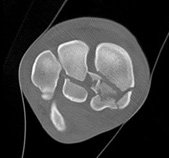

CT

A CT (Computer Tomography) tulajdonképpen egy szuper okos röntgen. Röntgensugarakat használ, de nem csak egy-két irányból készít felvételeket, hanem körbe-körbe haladva sok felvételt készít, melyet utána elemez, és képpé formál. A mai informatikai lehetőségekkel olyan komoly szoftverekkel látják el ezeket a gépeket, amelyekkel hihetetlen sok információt kaphatunk a hagyományos RTG felvételekhez képest. A kapott képek „felszeletelik” az adott testrészt, de térbeli ábrázolásra is képesek. Bár a CT a lógyógyászatban a fej vizsgálatának a legfontosabb módszere (fogak, orrüregek betegségeinek vizsgálatánál), az ortopédiában is hasznos, elsősorban repedések, törések leképezésénél. Egyes eseteknél a hagyományos röntgenfelvételekről nem lehet elég információhoz jutni, míg a CT mindezt kirázza a kisujjából.

A lábtőízület kis csontjainak vizsgálata A jobb alsó csont törött.